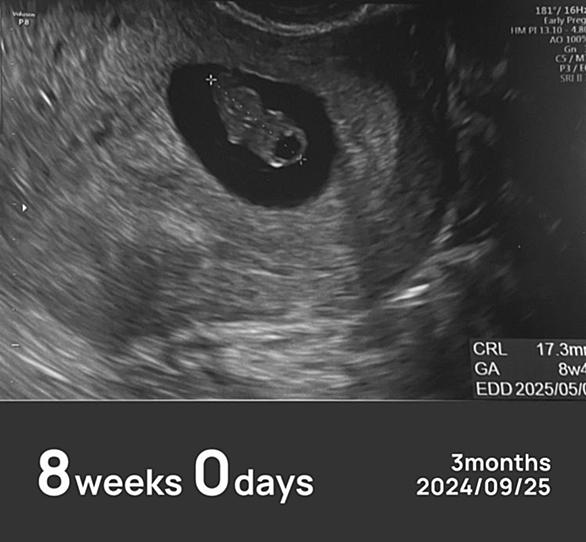

今日は妊娠7週3日目。2回目の心拍確認のため、不妊治療クリニックへ行ってきました。診察では、赤ちゃんの胎芽の大きさが 10mm にまで育っていて、しっかりと心拍も確認できました。小さな命がちゃんと育ってくれていることに、胸がいっぱいです。そして先生からは、「次の検診で問題がなければ、卒業ですね」との言葉が…!ついに、次回の診察で 不妊治療クリニックを卒業予定 となりました🌸通い始めてから1年半。採卵・移植・薬の副作用・通院スケジュールに追われた日々……思い返すと、いろんなことがありました。卒業の実感はまだないけれど、「ここまで来たんだ」としみじみ感じています。 🤰つわりが本格的にスタート ここ…